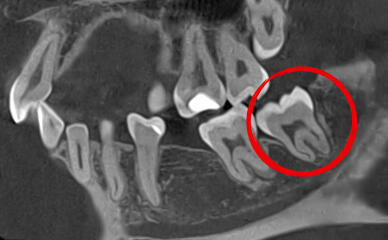

Перед удалением стоматолог назначает рентген (X-ray) или компьютерную томографию (КТ) для оценки положения зуба и анатомических особенностей, особенно в случае непрорезавшихся или неправильного положения зубов.

Непрорезавшиеся зубы мудрости часто имеют аномалии, которые усложняют удаление, такие как разветвленные, изогнутые корни или разрушенные коронки, что затрудняет захват щипцами. Для правильного удаления необходимы рентгеновский снимок и полный медицинский анамнез пациента.